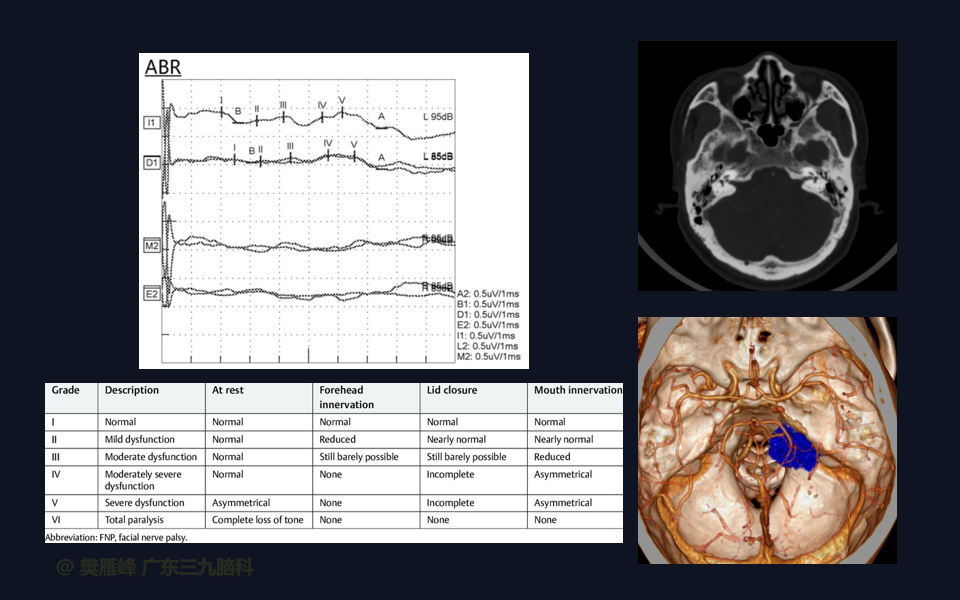

面神经功能障碍是显微手术切除的主要神经系统并发症。经迷路和乙状窦后入路的次全切除和近全切除相对于全切除显示了更好的术后面神经结果。完全切除肿瘤是和面听神经保存之间的妥协,是所有神经外科医生和所有患者在治疗前都应做好充分的准备。

在这个二维手术视频中,展示了一种经枕下乙状窦后入路束膜下分离保留面神经的方法。患者是一名51岁的男性,有1年右耳听力下降伴耳鸣、无步态不平衡病史,术前有右侧轻度面瘫,神经影像学显示右侧桥小脑角区约30×30×29mm的囊实性占位,增强后实性部分及囊壁可见明显强化。他接受了经乙状窦后入路保留面神经的方法,术中肿瘤全切除,面神经被肿瘤挤压成薄膜状覆盖于三叉神经表面。术后面瘫加重,听力未能保留,神经影像学显示肿瘤全部切除。我们展示了安全的颅神经保护和肿瘤切除的细微差别和技术要点,以及手术技术。